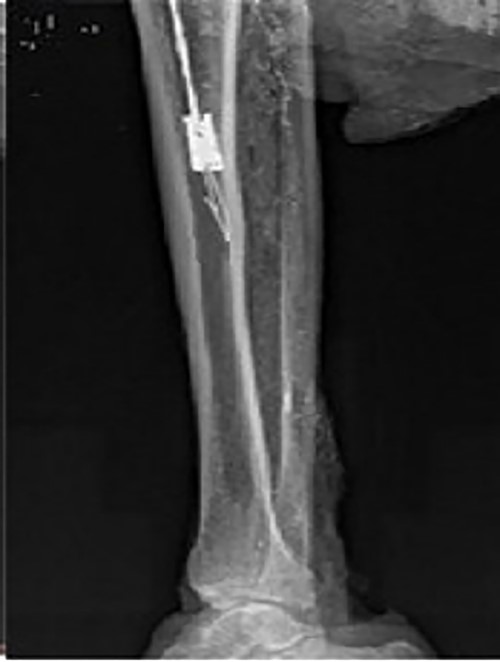

Intraoperative X-ray showing that the broken nail extractor was inserted into the medullary cavity and passed through the canal of the broken nail.

For the removal procedure, we made a hole at the entry point of the tibia for the intramedullary nail, inserted the guide needle and reamed the tibial medullary cavity with a Φ 11 mm drill bit along the guide needle (Fig. 3). The residue was flushed and aspirated after reaming. We adjusted the diameter of the barb on the spear of the homemade minimally invasive broken nail extractor to 3 mm, then inserted it into the medullary cavity and passed the nail extractor through the canal of the broken nail (Fig. 4). When the extractor was pulled back, the barb hooked the canal wall (Fig. 5) and successfully extracted the broken nail (Fig. 6). The operation was performed under fluoroscopy.